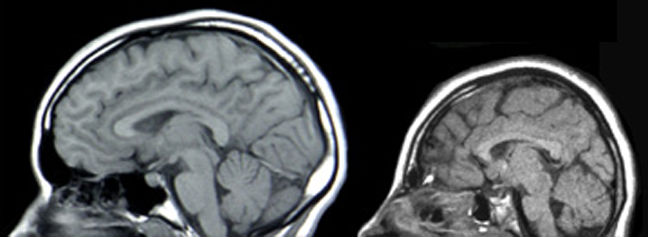

Saiba mais sobre o zika vírus

Entenda como acontece a transmissão e quais são os sintomas do vírus, que tem ligação direta com casos de microcefalia no país